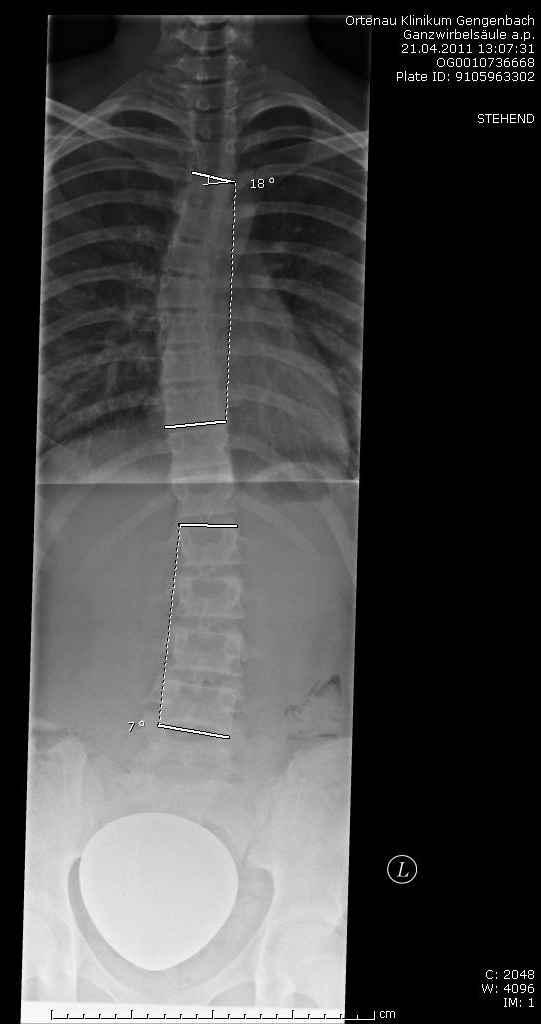

Also ich bin neu hier und vor einem Monat habe ich meine Skoliose bemerkt. Mein Arzt hat am Anfang (bevor es geröngt wurde) gesagt, es sei nur eine leichte Skoliose. Aber als er dann das Röntgenbild gesehen hat, war er erstaunt: ich hatte 2 "Wellen" in meiner WS, einmal 20° und einmal 7°. Eigentlich hätte ich dann ein Korsett bekommen aber er wollte es mir ersparen und hat diese Werte "schön gerechnet" und jetzt habe ich anstatt 20° nur 18°, muss jetzt erstmal nur KG machen und soll in einem halben Jahr wieder kommen, um zu gucken, wie es geworden ist. Wenn es so bleibt, darf ich selber entscheiden, ob ich ein Korsett bekomme. Wenn es schlimmer wird, ist mir diese Entscheidung schon abgenommen. Und jetzt hab ich mal ein paar Fragen an euch: